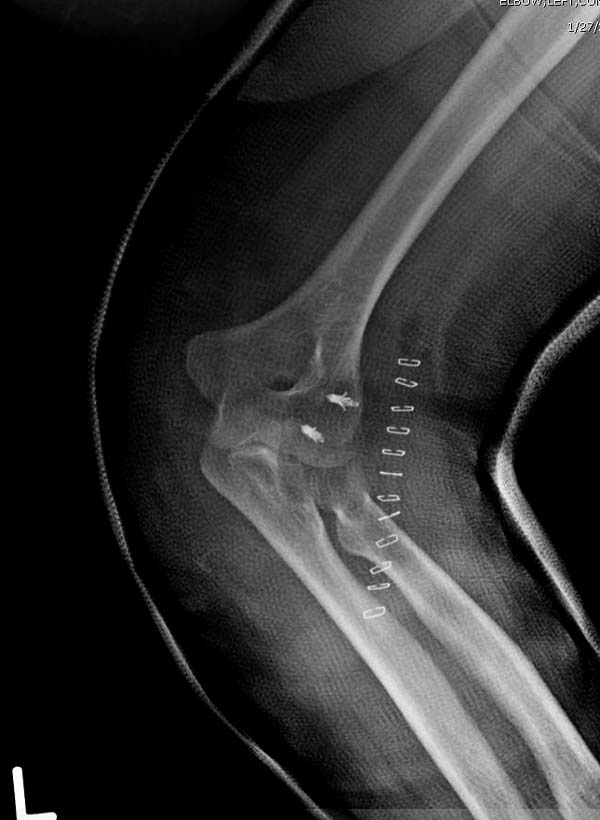

Для примера здесь случай начатый в другом центре, а потом переправленный к нам.

Снимки: 1-2 вывих, 4-5 вторичное смещение в гипсе, реконструкция латеральной связки и капсулы 13-14, повторный вывих после реконструкции, перевод в наш центр; 18-21 временная фиксация, 22-25 трансартикулярная фиксация и нестабильная головка фиксирована спицами, 29-30 амбулаторно, 32-33 после удаления винта и спиц...